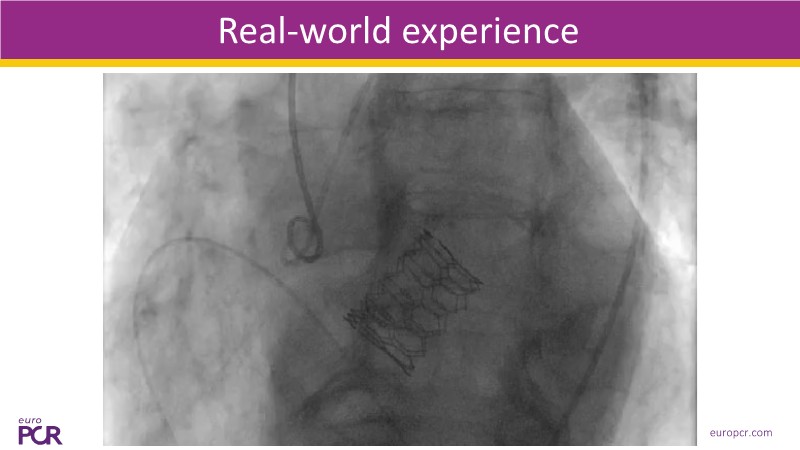

This session presents the latest updates on the novel Myval Octapro transcatheter heart valve (THV), based on one year of real-world clinical experience. Experts share practical tips and clinical cases that highlight how this innovative device can improve TAVI patient outcomes. The session also addresses imaging and sizing strategies critical for TAVI planning, as well as procedural best practices for successful implantation of the Myval Octapro THV.

- To learn from the experts best-in-the-class TAVI practice: pre-procedural (imaging, sizing rationale, treatment strategy), procedural tips and tricks and post-procedural management

- To know about the novel Myval Octapro THV - Key features, the procedural impact and potential clinical benefits